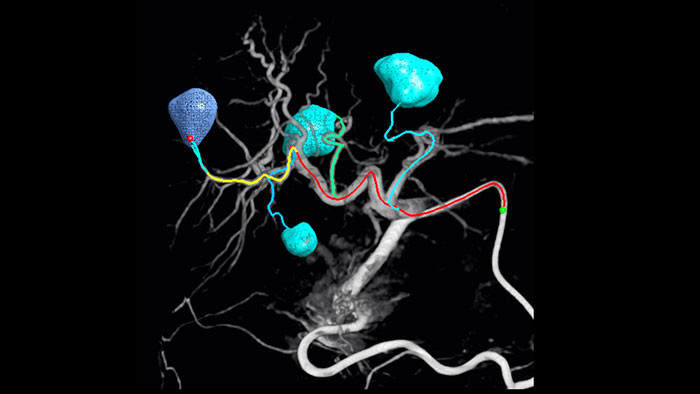

La adopción de técnicas de quimio/radioembolización como TACE y SIRT genera la necesidad de estandarización y eficiencia. Caso tras caso, debe localizar de manera fiable y coherente los tumores, identificar todos los vasos nutricios y planificar/ejecutar el método intervencionista adecuado. Nuestra solución de detección automática de vasos nutricios puede mejorar significativamente la detección de la arteria nutricia en comparación con el uso de CT de haz cónico únicamente. EmboGuide permite maximizar la eficacia de sus procedimientos de TACE, ya que mejora potencialmente su sensibilidad, reduce los falsos positivos y maximiza la concordancia entre evaluadores.1

La capacidad de detectar y diferenciar los nódulos hepáticos e identificar los pequeños vasos nutricios es fundamental para determinar el tratamiento adecuado. Navegar a la región de interés alcanzando todos los vasos nutricios, sin dejar de ser selectivo con la lesión, aumenta las posibilidades de éxito. La confirmación del criterio de valoración del tratamiento y el éxito del tratamiento mientras el paciente aún se encuentra en la mesa aumenta la confianza en los resultados clínicos.